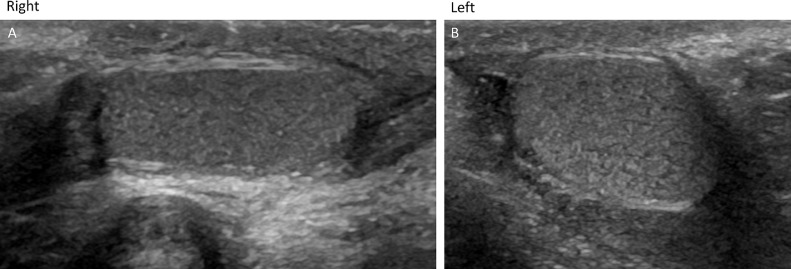

Ultrasound of the penis and scrotum (Fig. 2) demonstrated well-developed right penis, with normal corpora spongiosum and normal separate corpora cavernosa each supplied by separate cavernosal artery. Left penis demonstrated normal corpora spongiosum, and 2 separate corpora cavernosa supplied by 1 cavernosal artery. Undescended well-developed testes were also seen in the inguinal canal (Fig. 3). Doppler imaging demonstrated normal flow to both the testes.

Fig. 3.

Undescended well-developed testes noted in the inguinal canal. Doppler imaging demonstrated normal flow to both the testes (not shown in the figure).